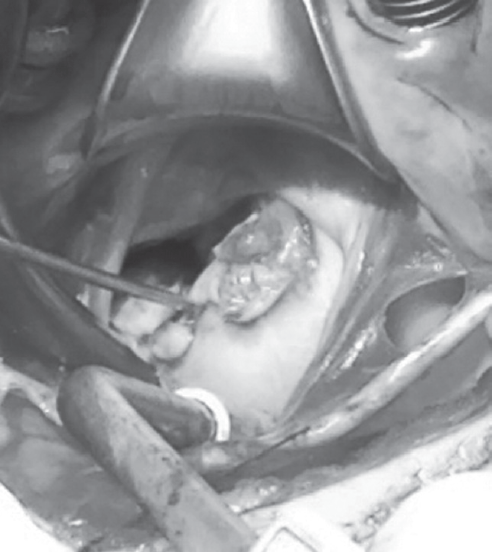

Интраоперационно: левая атриотомия. В области задней створки митрального клапана (Р2) определяется абсцесс 1 × 1 см, вегетация 1,5 × 1,5 см с тромботическими массами, фиксированная к створке митрального клапана (рис. 7, 8). В области передней створки митрального клапана (А2, А3) определяются вегетации от 0,5 до 1 см с тромботическими массами с распространением на опорные хорды и подклапанный аппарат. Абсцесс задней створки вскрыт, санирован. Створки митрального клапана иссечены по периметру фиброзного кольца МК с оставлением части подклапанных структур задней створки. Санация камер сердца. Вшит механический протез МедИнж 27 мм.

Рис. 7. Интраоперационное фото. Абсцесс на задней створке митрального клапана

Fig. 7. Intraoperative photo. Abscess on the mural leaflet of the mitral valve

Рис. 8. Макропрепарат: створки удаленного митрального клапана с вегетациями.

Примечание. Фрагменты створок МК 3 × 2 см и 2,5 × 1 см с множественными «бородавками» серо-розового цвета (6 штук). На задней створке — свежие тромботические массы с переходом их на хордальные нити. Створки клапана неравномерно утолщены, режутся с трудом. На передней створке — тромботические массы меньше и стенка более тонкая

Fig. 8. Deleted mitral valve’s leaflets with vegetations.

Note. Gross appearance of phragments of mitral valve’s leaflets 3 × 2 cm and 2.5 × 1 cm with multiple warts gray-pink color (6 pieces). On the back leaflet – fresh thrombotic masses with their transition to chordae tendineae. The valve leaflets are unevenly thickened and are difficult to cut. On the anterior leaflet-the thrombotic masses are smaller and the wall is thinner